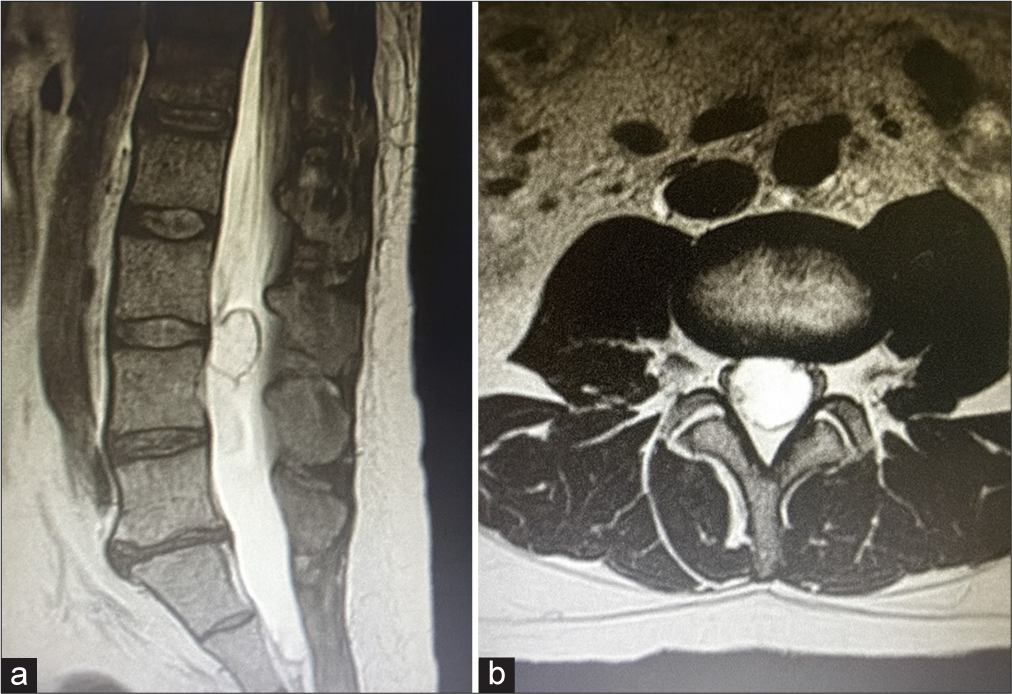

Imagem 1: Ressonância magnética pré operatória (cortes sagital e axial) mostrando uma lesão intradural extramedular bem definida na coluna lombar.

A ressonância magnética da coluna lombar revelou uma lesão intradural extramedular ao nível lombar, com características compatíveis com um tumor da bainha nervosa. A compressão das estruturas neurológicas explicava o quadro clínico e justificava a necessidade de uma abordagem cirúrgica atempada.